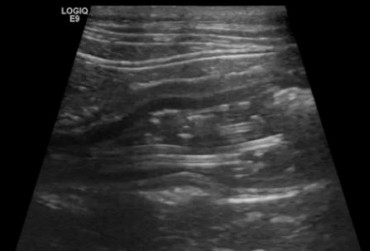

Kot syberyjski, samiec, 4l. Robaczyca jelit cienkich.

24 czerwca 2019

Wojciech Atamaniuk

Czytaj więcej